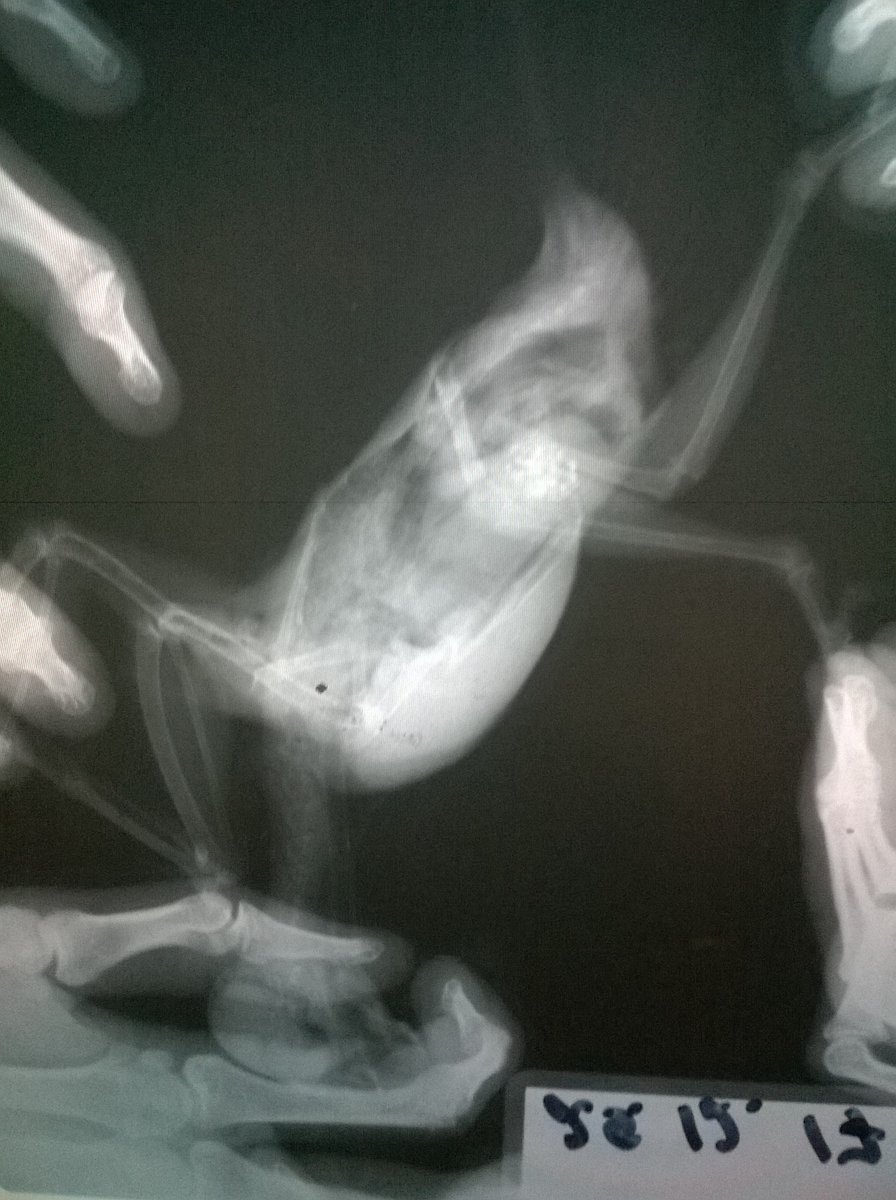

Возраст: 7 полных лет. Пол: женский. Порода: сизарь обыкновенный (Columba livia). Около 4-х месяцев назад голубка перестала нести яйца. Последние две пары снесенных яиц были значительно меньше обычных (не более 2 см.). Затем (в конце июля) появились странные выделения в помете (фото 1 и 2). Такие выделения начали выходить вместе с пометом примерно 1-2 раза в месяц. Когда у нее появляются эти странные выделения она ведет себя примерно так же, как во время кладки (хвост опущен, ищет место для кладки, разгребает, учащенно дышит). В остальное время голубка жизнерадостная и активная, ест и пьет хорошо, как обычно, летает, общается и т.д. Мы были у ветеринара, ей сделали рентген (фото 3 и 4). Доктор сказала, что у нее в брюшке эти сгустки - предположительно, остатки несформированного яйца. Эти сгустки могут накапливаться и давить на органы. Доктор предложила два способа решения: Инъекция (чего именно мы не знаем). При помощи этой инъекции, предположительно, голубка должна самостоятельно избавиться от этих сгустков, которые выйдут самостоятельно. Доктор сказала, что понаблюдает за ней в течение половины дня. Оперативное вмешательство. Если инъекция не подействует - доктор сказала что нужно будет делать операцию по очистке. Но при операции есть риск неудачного исхода. В общем от операции, над инъекцией думаем. Хотим собрать мнение еще нескольких специалистов, т.к. очень боимся возможного риска и не хотим сделать хуже. Пишу сюда, потому что хочу узнать мнения людей, встречавшихся с подобными ситуациями и так же мнения орнитологов и\или голубеводов, присутствующих на этом форуме. Заранее спасибо всем за ответ!- 3 ответа

Неразлучник перестал летать, когда посмотрела, обнаружила на внутренней стороне крыла шишечку, сделали рентген, фото прикладываю. Не летает, крыло отпустилось и дрожит, продолжается больше месяца, обратиться больше не к кому, у нас нет специалистов в городе. Помет у попугая не менялся, активность хорошая, кушает тоже хорошо -

г.Новодвинск. Специалистов нет. Проблема: плохо ходит, падает, не ест. Помет изменился. Предположение: застревания яйца Попугай корелла самка 6 лет. Клеточное содержание. Практически без выпуска из-за собаки,детей.Неслась практически ежегодно. Корм только РИО для средних попугаев, не ограничено. Съедала много.Пила воды много. Овощи, зелень, мин.подкормка,сепии и т.п. в рационе отсутствовали. На окне в клетке в комнате. Проблемы начались в начале недели, после того как снесла яйцо. Упала с жердочки, и практически перестала ходить. Обратились к девушке волонтеру по птицам. Единственному человеку который хоть как то попытался помочь и отправил сюда. Рекомендовано: Рентген(сделан), анализы( бак.посев,копрограмма) НЕ ДЕЛАЮТ в гор.вет.лаб. Обратиться к специалисту(поэтому тут). Улучшить условия кормления и содержания(делаем). Помогите спасти птицу,пожалуйста.Ошибки осознали..исправим,но очень нужна помощь. Назначено: вазелиновое масло 0,4мл в клоаку, 0,1мл в клюв 1 раз в сутки. . Водяная баня. Кормление насильно через шприц запаренной крупой с яблочным пюре детским. Глюконат кальция ампульный по 0,05мл 1 раз в сутки, клюв. Мильгамма 1/8 таблетки в клюв. Энтеросгель 0,1мл в разведении 1:1 с водой. Нужна помощь в лечении(